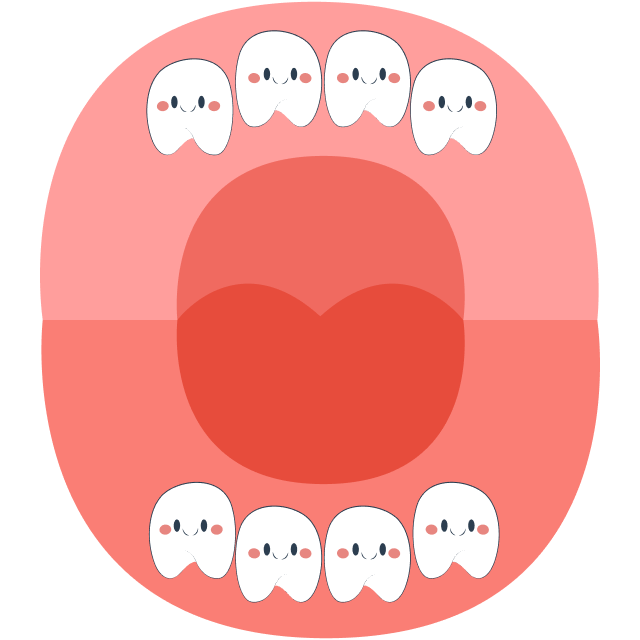

At around 6 years old, children prepare to lose their first tooth, and primary (baby) teeth will gradually be replaced by permanent teeth. The tooth replacement sequence typically begins with the eruption of the first molar (tooth number 6) and ends with the eruption of tooth number 7 around the age of 12.

During this stage, parents should closely monitor their child’s tooth replacement process and schedule regular dental check-ups. This helps detect common abnormalities early, such as missing tooth buds, extra teeth in the midline gap, or impacted teeth (mesiodens), which can obstruct tooth eruption and affect the positioning of the remaining teeth.